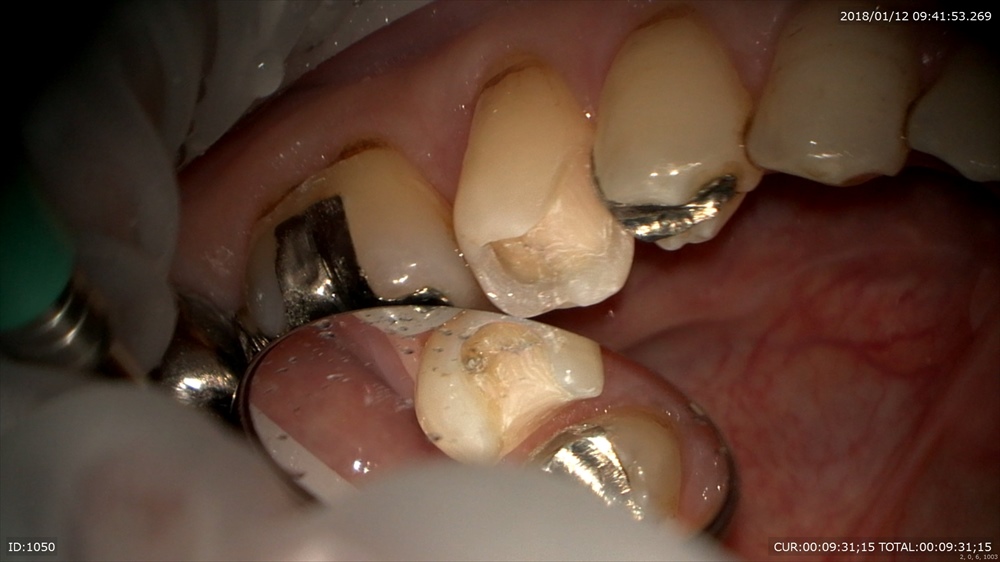

次は精密根管治療

2本同時に治療中

右が術前左が術後綺麗になってきました。

根管の先まで見えます。マイクロスコープでしか確認ができません。痛みがとれない。ばれが引かないなど必ず原因があるはずです。

次回最終的なお薬ですね。4回で終了。ちょっと回数かかりすぎです。反省。